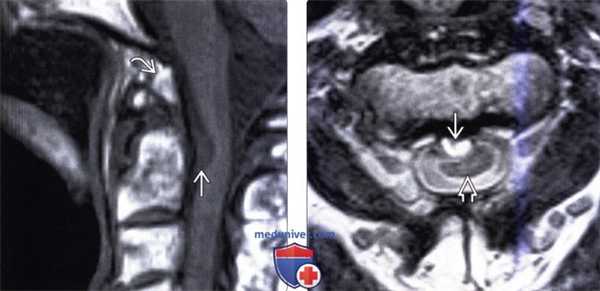

(Слева) Т1 -ВИ, сагиттальная проекция, FS+КУ: не накапливающее контраст экстрадуральное кистозное образование в области КВС, являющееся причиной компрессии соседнего участка спинного мозга. Обратите также внимание на имеющиеся признаки врожденной аномалии КВС.

(Справа) Это аксиальное Т2-ВИ подтверждает диагноз нейроэнтеральной кисты, выполняющей задне-боковой отдел спинномозгового канала и смещающей шейный отдел спинного мозга ЕЕ вперед и влево.

(Слева) Т1-ВИ, сагиттальная проекция (синдром Клиппеля-Фейля): небольшая вентральная интрадуральная экстрамедуллярная нейроэнтеральная киста, сдавливающая вентральную часть спинного мозга. Также на этом изображении видна зубовидная кость.

(Справа) На аксиальном Т2-ВИ у пациента с синдромом Клиппеля-Фейля выявлена небольшая гиперинтенсивная экстрамедуллярная нейроэнтеральная киста, деформирующая и смещающая кзади шейный отдел спинного мозга.